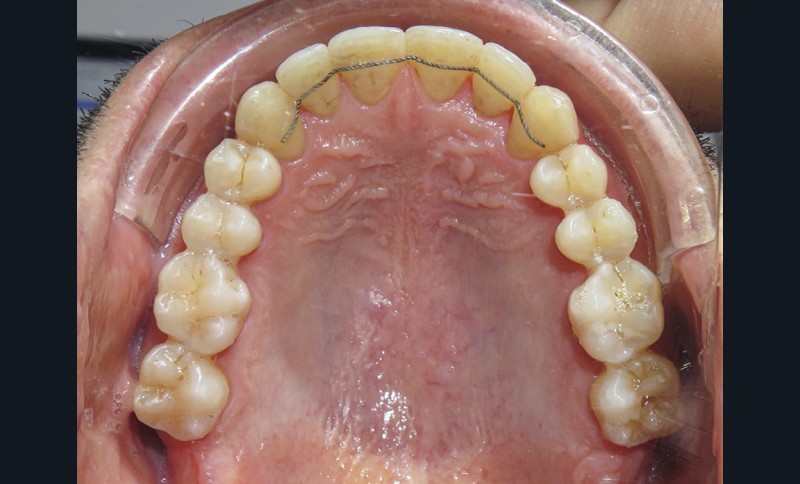

Dans un premier temps (fig. 2), la 28 (et la 18) a été extraite pour faciliter le déplacement de la 27 (DDM postérieure). Une minivis palatine a été placée entre 26 et 27 et des boutons ainsi qu’un sectionnel collés sur les faces vestibulaires des 26 et 27. Des chaînettes élastomériques ont été ancrées sur les boutons et la minivis, en passant au-dessous des faces occlusales de ces dents. Les chaînettes reliant un dispositif vestibulaire et un palatin et prenant appui sur les faces occlusales des molaires du secteur 2, les mouvements dentaires induits sont un déplacement vestibulo-palatin associé à une ingression des 26 et 27. Les minivis sont des ancrages absolus qui ne nécessitent pas d’utiliser l’ancrage des dents adjacentes ou antagonistes, ce qui préserve d’effets sur ces dernières.